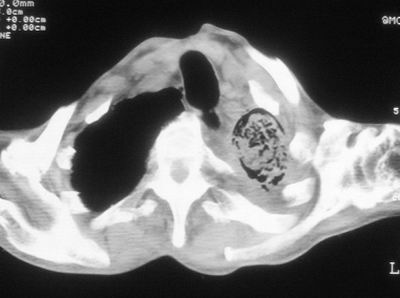

标题: CT11864:男,47岁,反复咳嗽、咯痰、咯血3年,请分析. [打印本页]

患者,男,47岁,反复咳嗽、咯痰、咯血3年,再发5天。痰培养未找到真菌、抗酸杆菌、癌细胞。

以下是引用xulianj在2008-2-25 21:01:00的发言:[br]左肺上叶结核伴肺纤维化有霉菌球形成,纵隔移位,左肺下叶感染性病变,建议抗炎抗结核后复查,双肺气肿.

考虑:左肺慢纤伴霉菌球形成、双肺全小叶型肺气肿。

1)考虑为:左肺上叶肺结核(空洞形成),伴左下肺感染;不排除霉菌感染可能。2)肺气肿。

左肺上叶结核伴肺纤维化空洞形成并左肺下叶感染,纵隔牵拉移位,建议作进一步检查排除左侧肺霉菌感染可能。